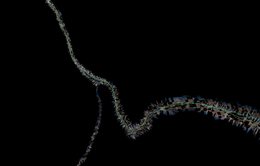

|

To evaluate our segmentation of the RCA, we compare our results to an expert segmentation and use the metrics proposed in the Rotterdam Coronary Artery Algorithm Evaluation Framework to quantify them.

Our segmentation overlaps more than 91% of the expert segmentation.

Before the first segmentation error occurs, our segmentation overlaps more than 83%.

Concerning the clinical relevant part of the vessel, our segmentation overlaps more than 91%. The clinical relevant part of the vessel is defined as parts where the vessel diameter is >= 1.5mm or parts which are laying distal than these ([Schaap2009]).

Accuracy AI: 0.307439, score: 44.9975 The average distance between our centerline and the expert segmentation is about 0.3 mm. |